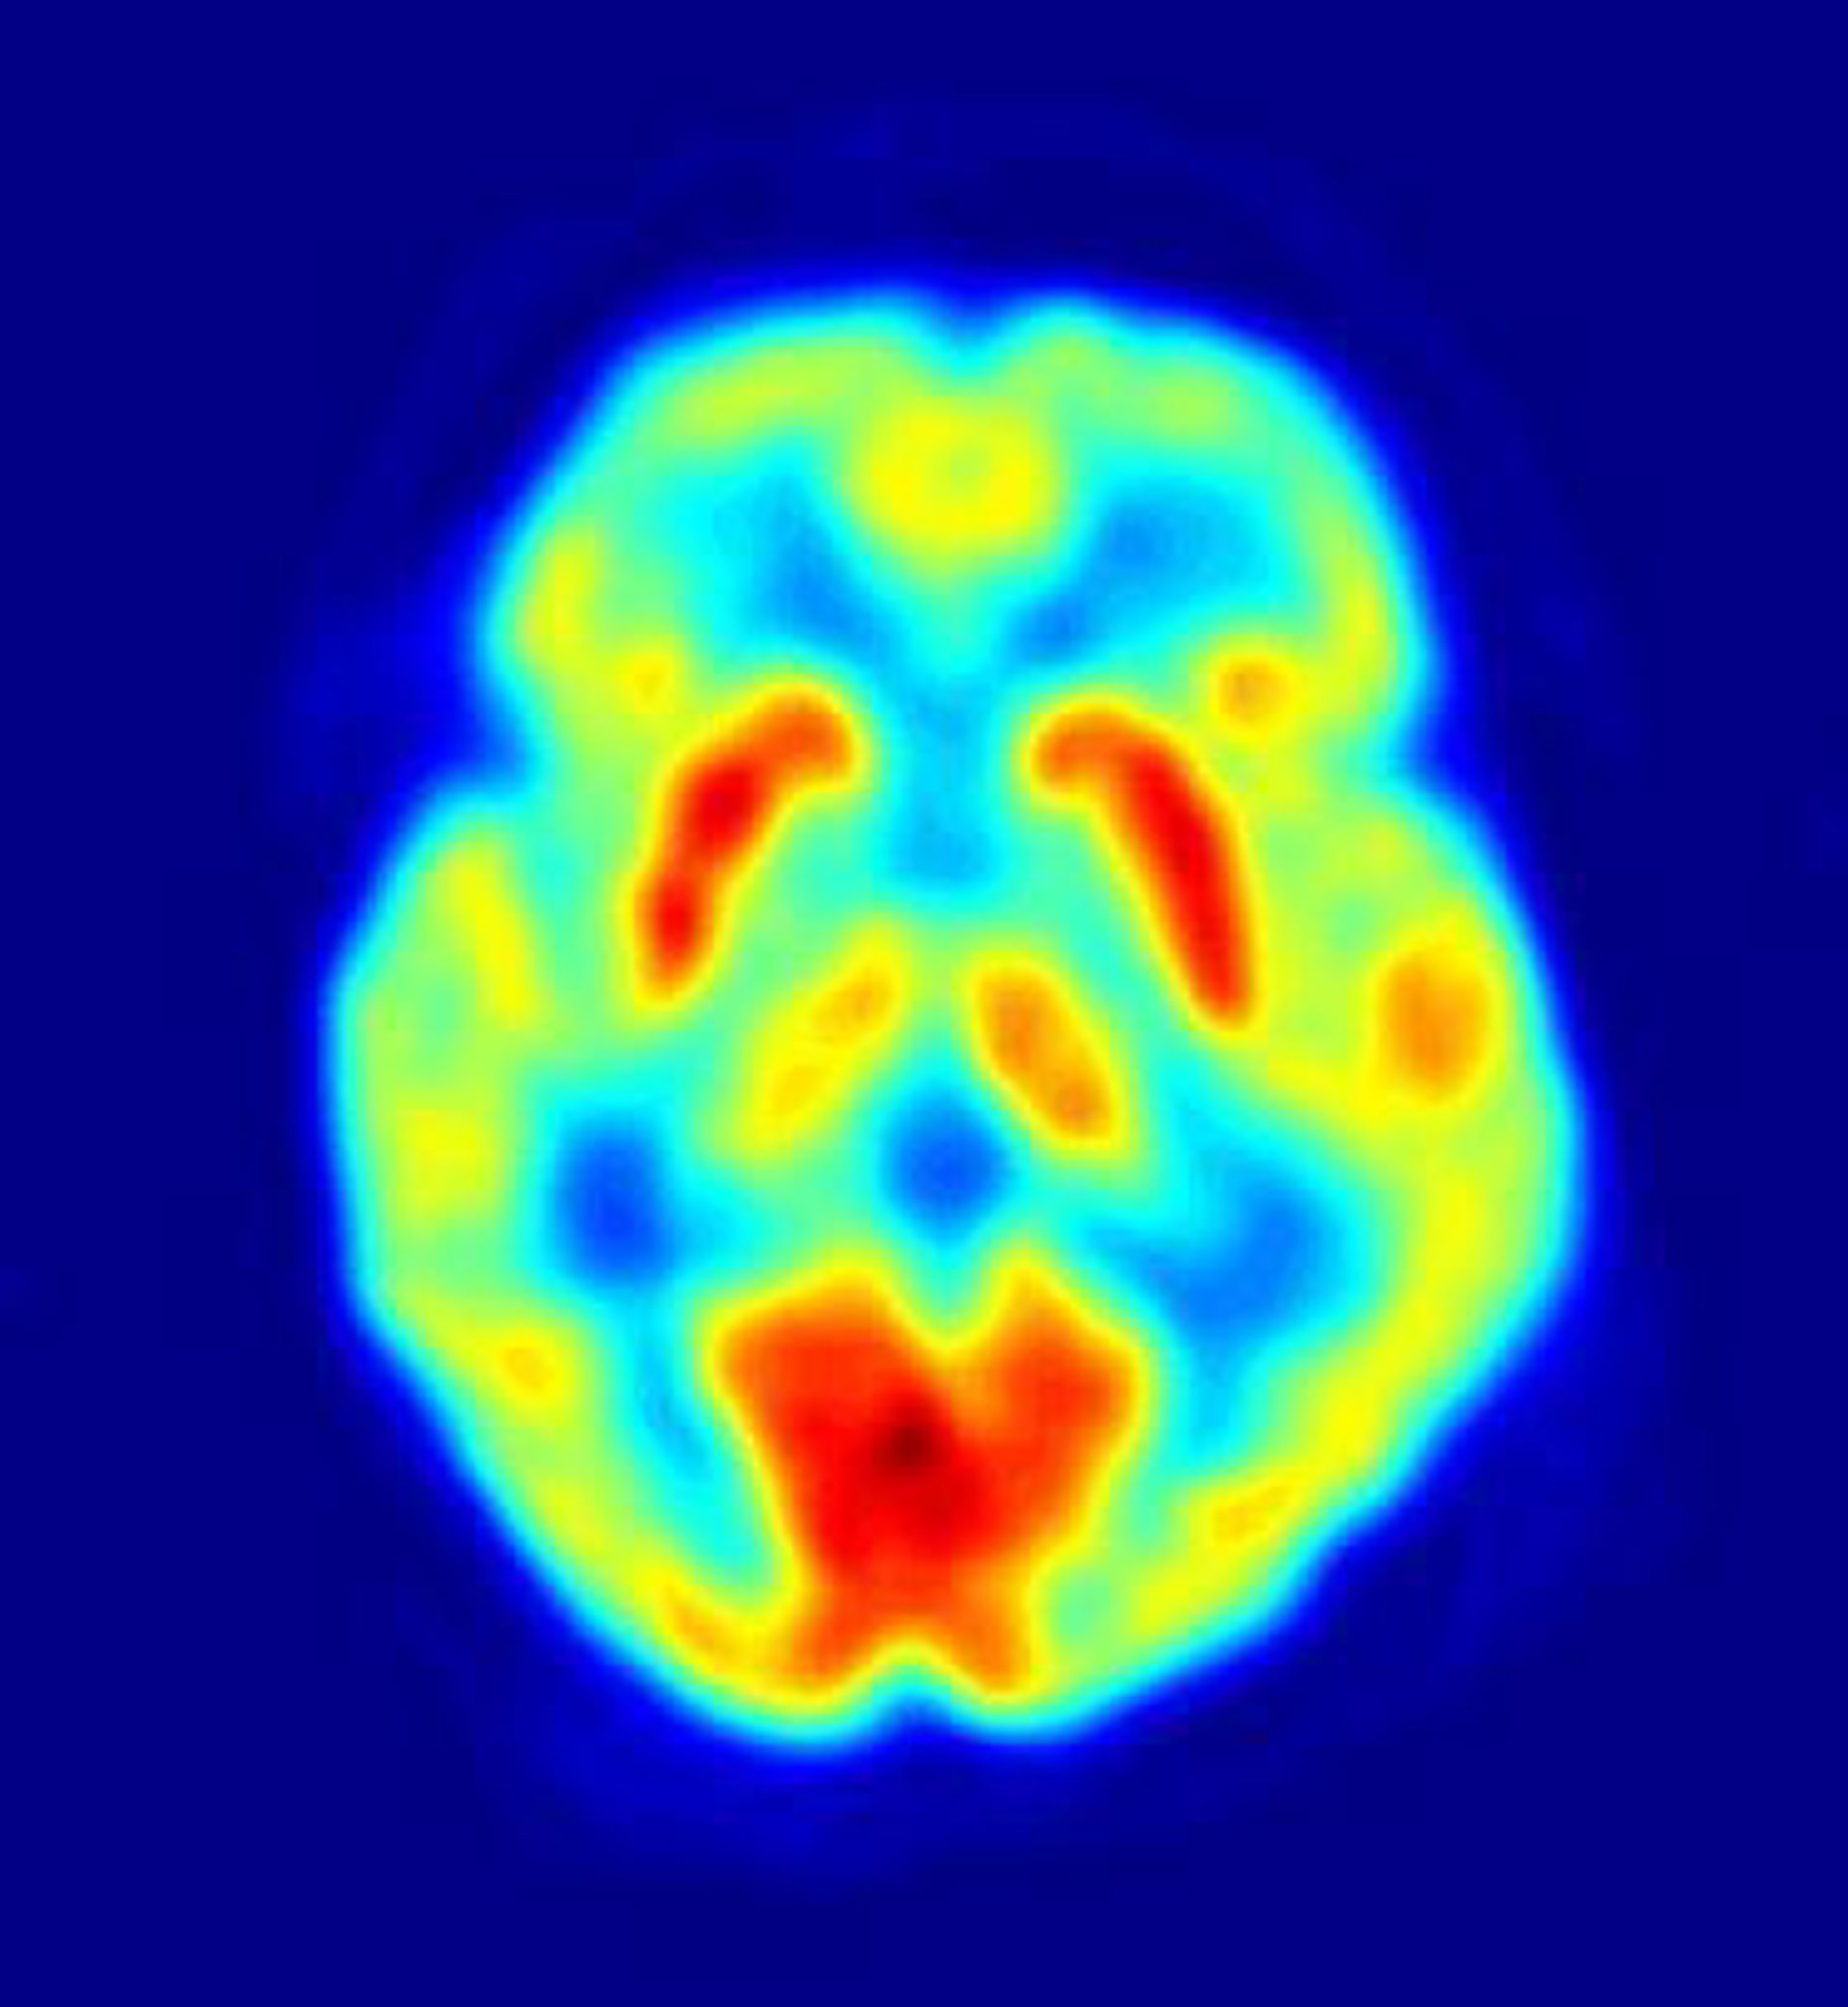

Según señalan los investigadores, las diferencias en la personalidad que surgen en relación a los sentimientos humanos de desigualdad modifican la actividad en la amígdala, una región cerebral importante para el procesamiento emocional automático. El estudio contradice ideas previas que sugieren que tales diferencias de personalidad se deben a diferencias en la corteza prefrontal.

Los investigadores descubrieron que la actividad en la amígdala difería entre estos dos grupos de personas y que la mayor recompensa desigual se asociaba con una mayor actividad de la amígdala en las personas prosociales. Por ello concluyen que la característica aversión prosocial a la desigualdad está vinculada a la actividad en la amígdala y no depende del control consciente de los impulsos egoístas.